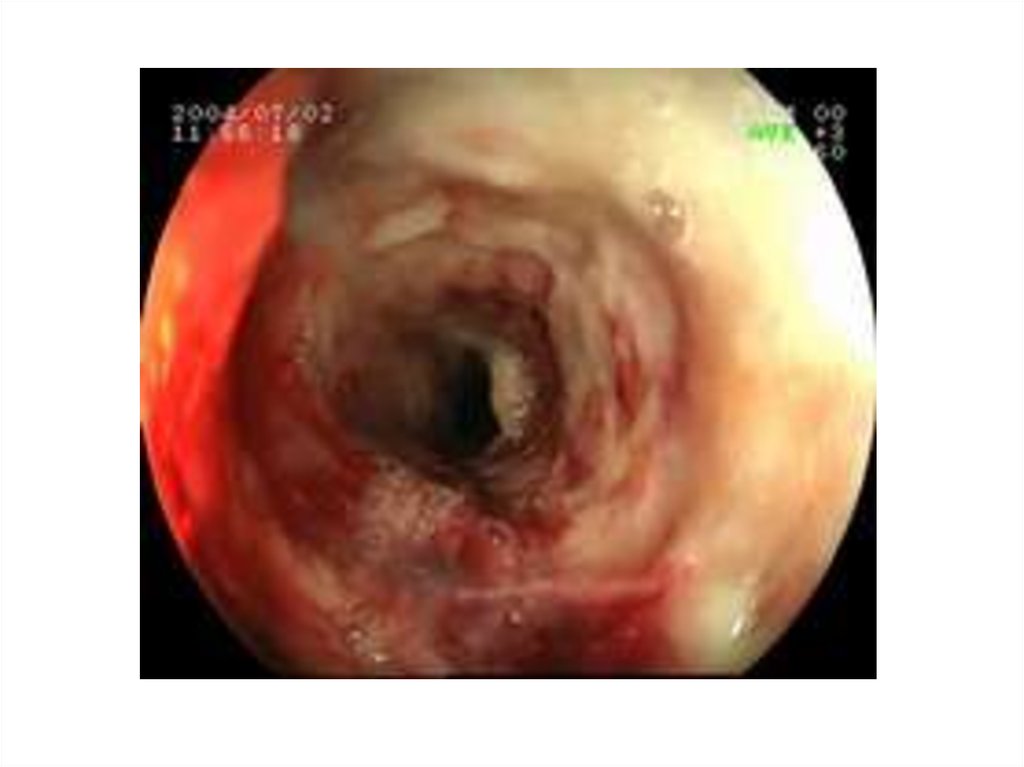

В зависимости от глубины

поражения различают 3 степени химического (и

термического) ожога пищевода.

• I степень характеризуется поражением

поверхностных слоев эпителия и выглядит как

гиперемия слизистой оболочки.

• II степень ожога приводит к некрозу

слизистой оболочки и образованию поверхностных язв.

• При III степени ожога поражается мышечный

слой с образованием глубоких язв,

отторжением слизистой оболочки и

кровотечением.